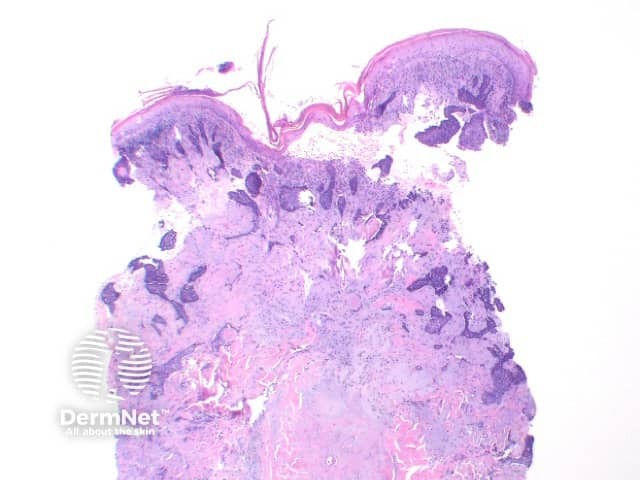

The key feature of basal cell carcinoma at low power magnification is of a basaloid epithelial tumour arising from the epidermis (figure 1). The basaloid epithelium typically forms a palisade with a cleft forming from the adjacent tumour stroma (figure 2). Centrally the nuclei become crowded with scattered mitotic figures and necrotic bodies evident (figure 3). A useful distinguishing feature from other basaloid cutaneous tumours is the presence of a mucinous stroma (figure 4). Some tumours may also show foci of regression, seen as areas of eosinophilic stroma with lack of basaloid nests.

Superficial BCC: This variant show multifocal nests of atypical basaloid epithelium arising as buds from the basal layer of the epidermis. These nests remain confined to the papillary dermis (Figure 5)

Figure 4

Figure 5